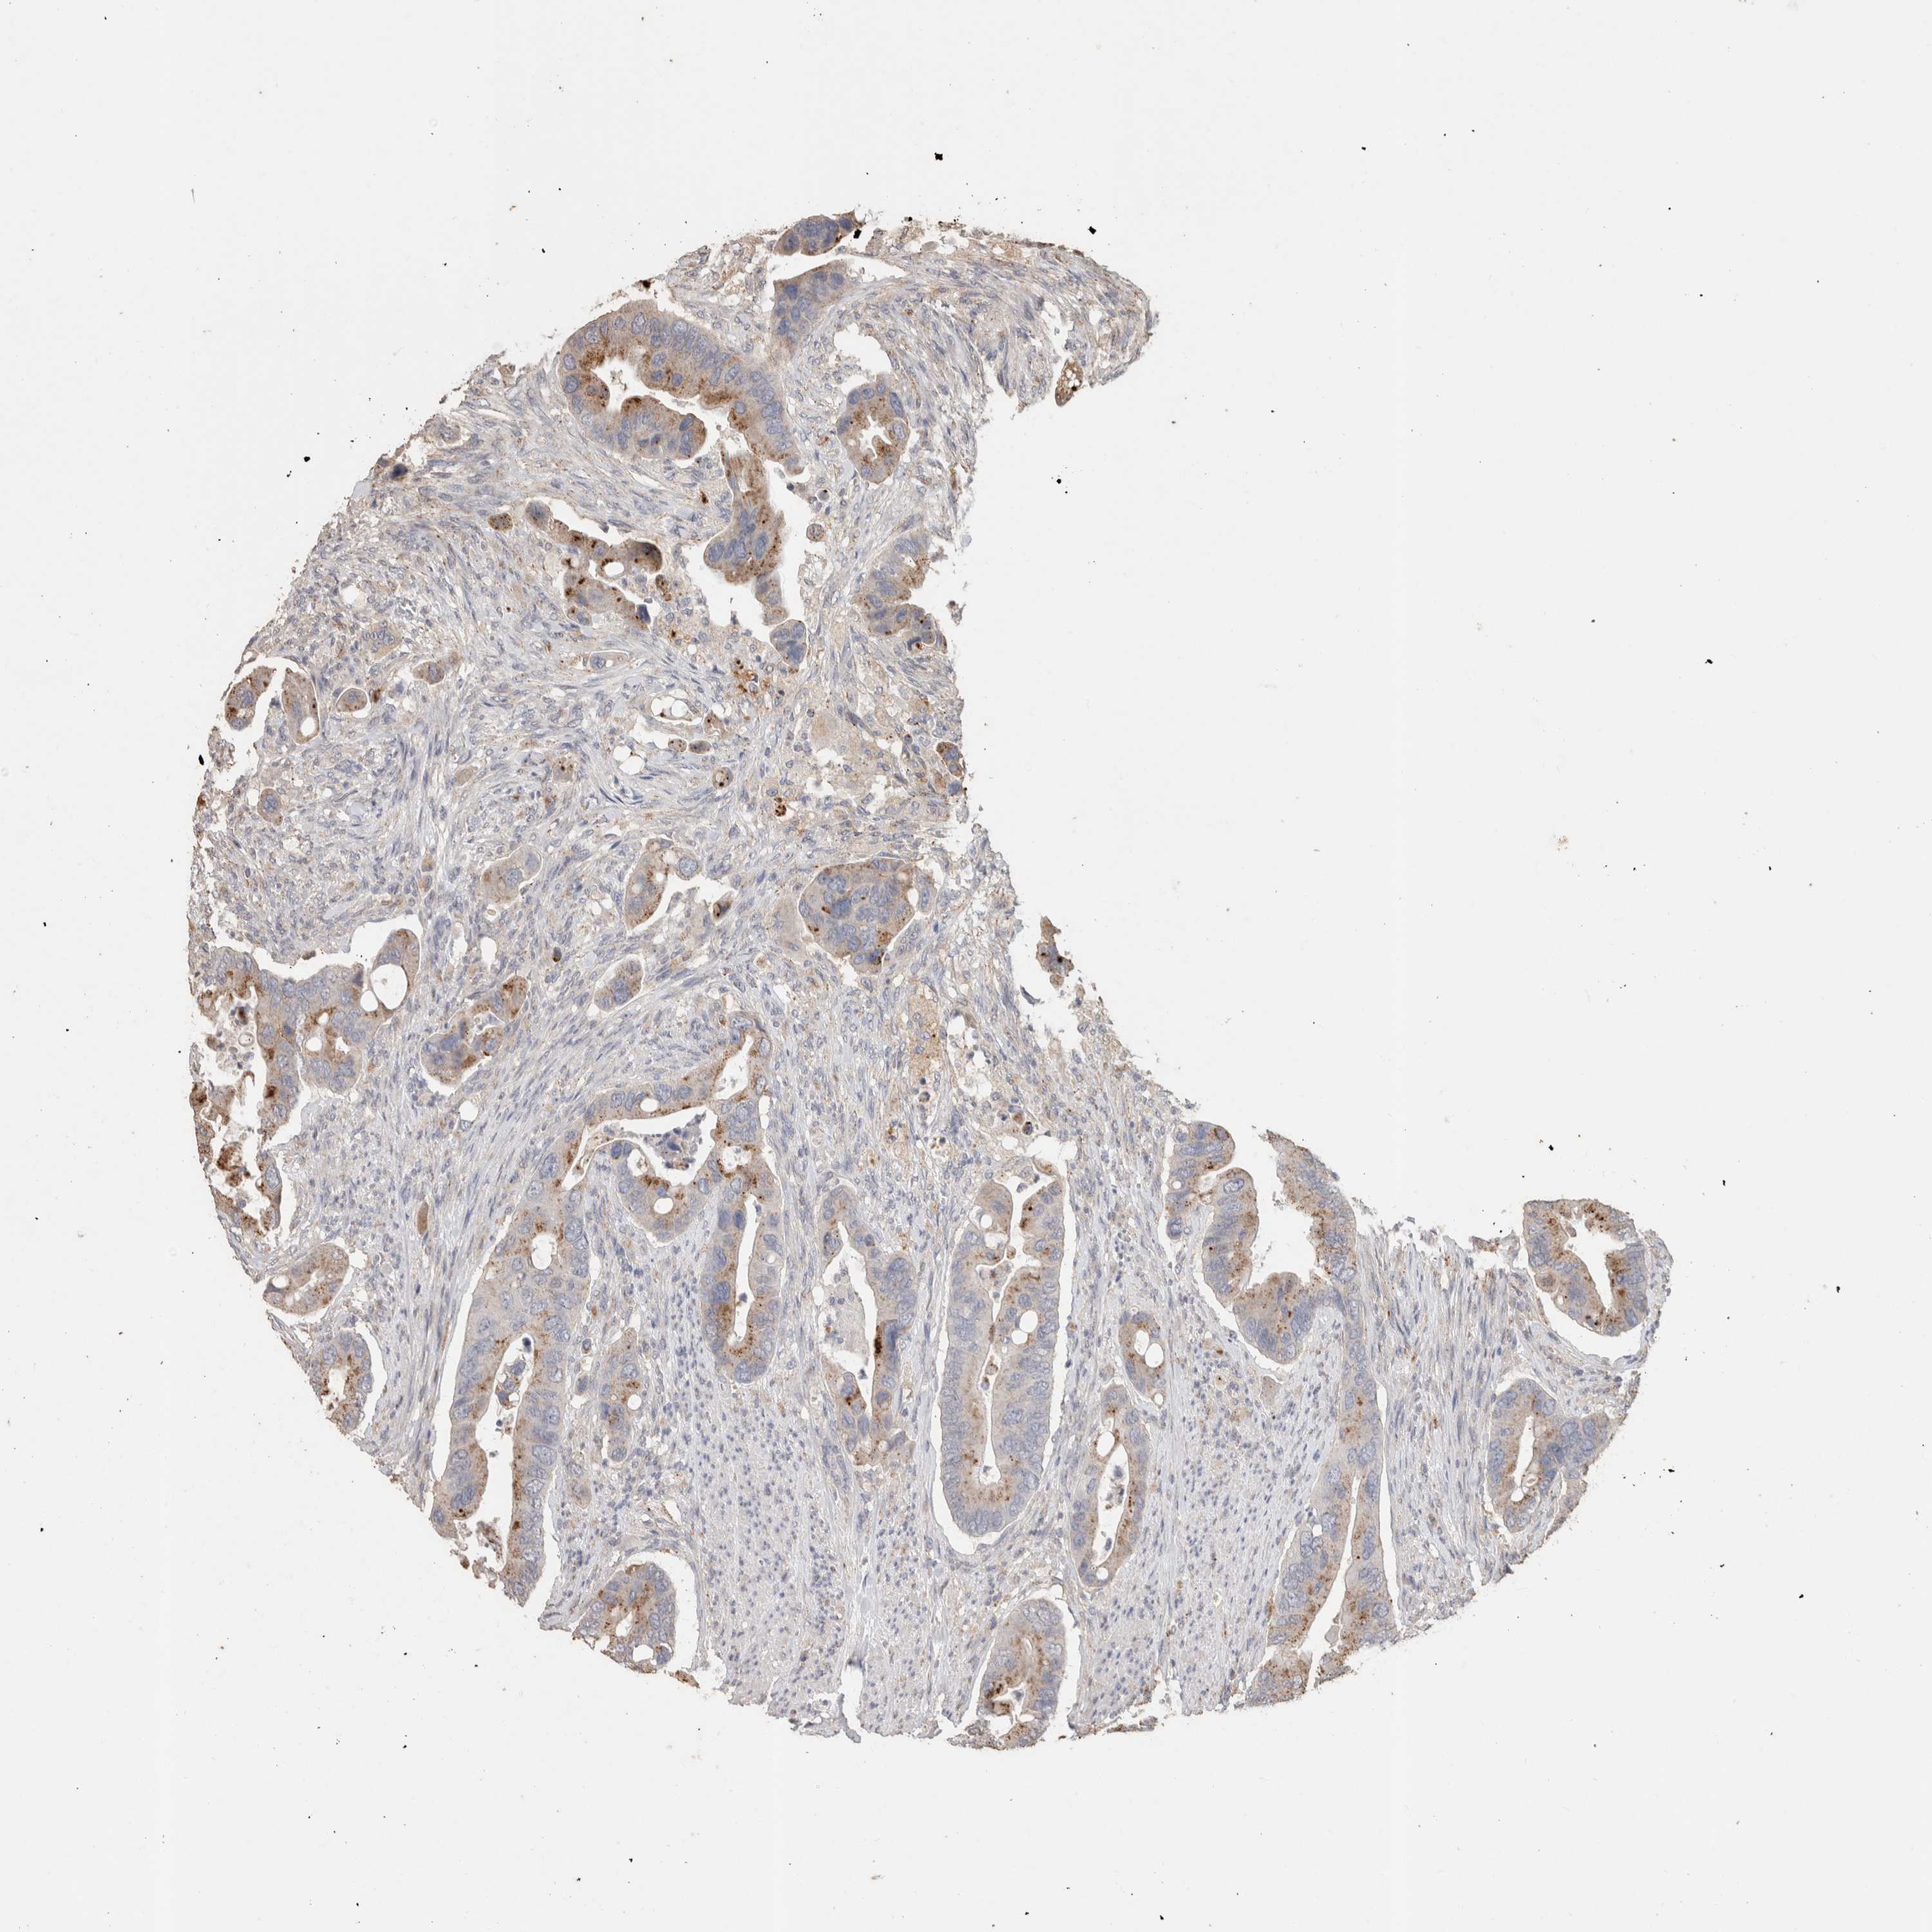

CANCER COLORECTAL CANCER Show tissue menu

COAD TCGA COAD VALIDATION READ TCGA READ VALIDATION PROTEIN COAD CPTAC PROTEIN EXPRESSION

ANTIBODIES

AND

VALIDATION